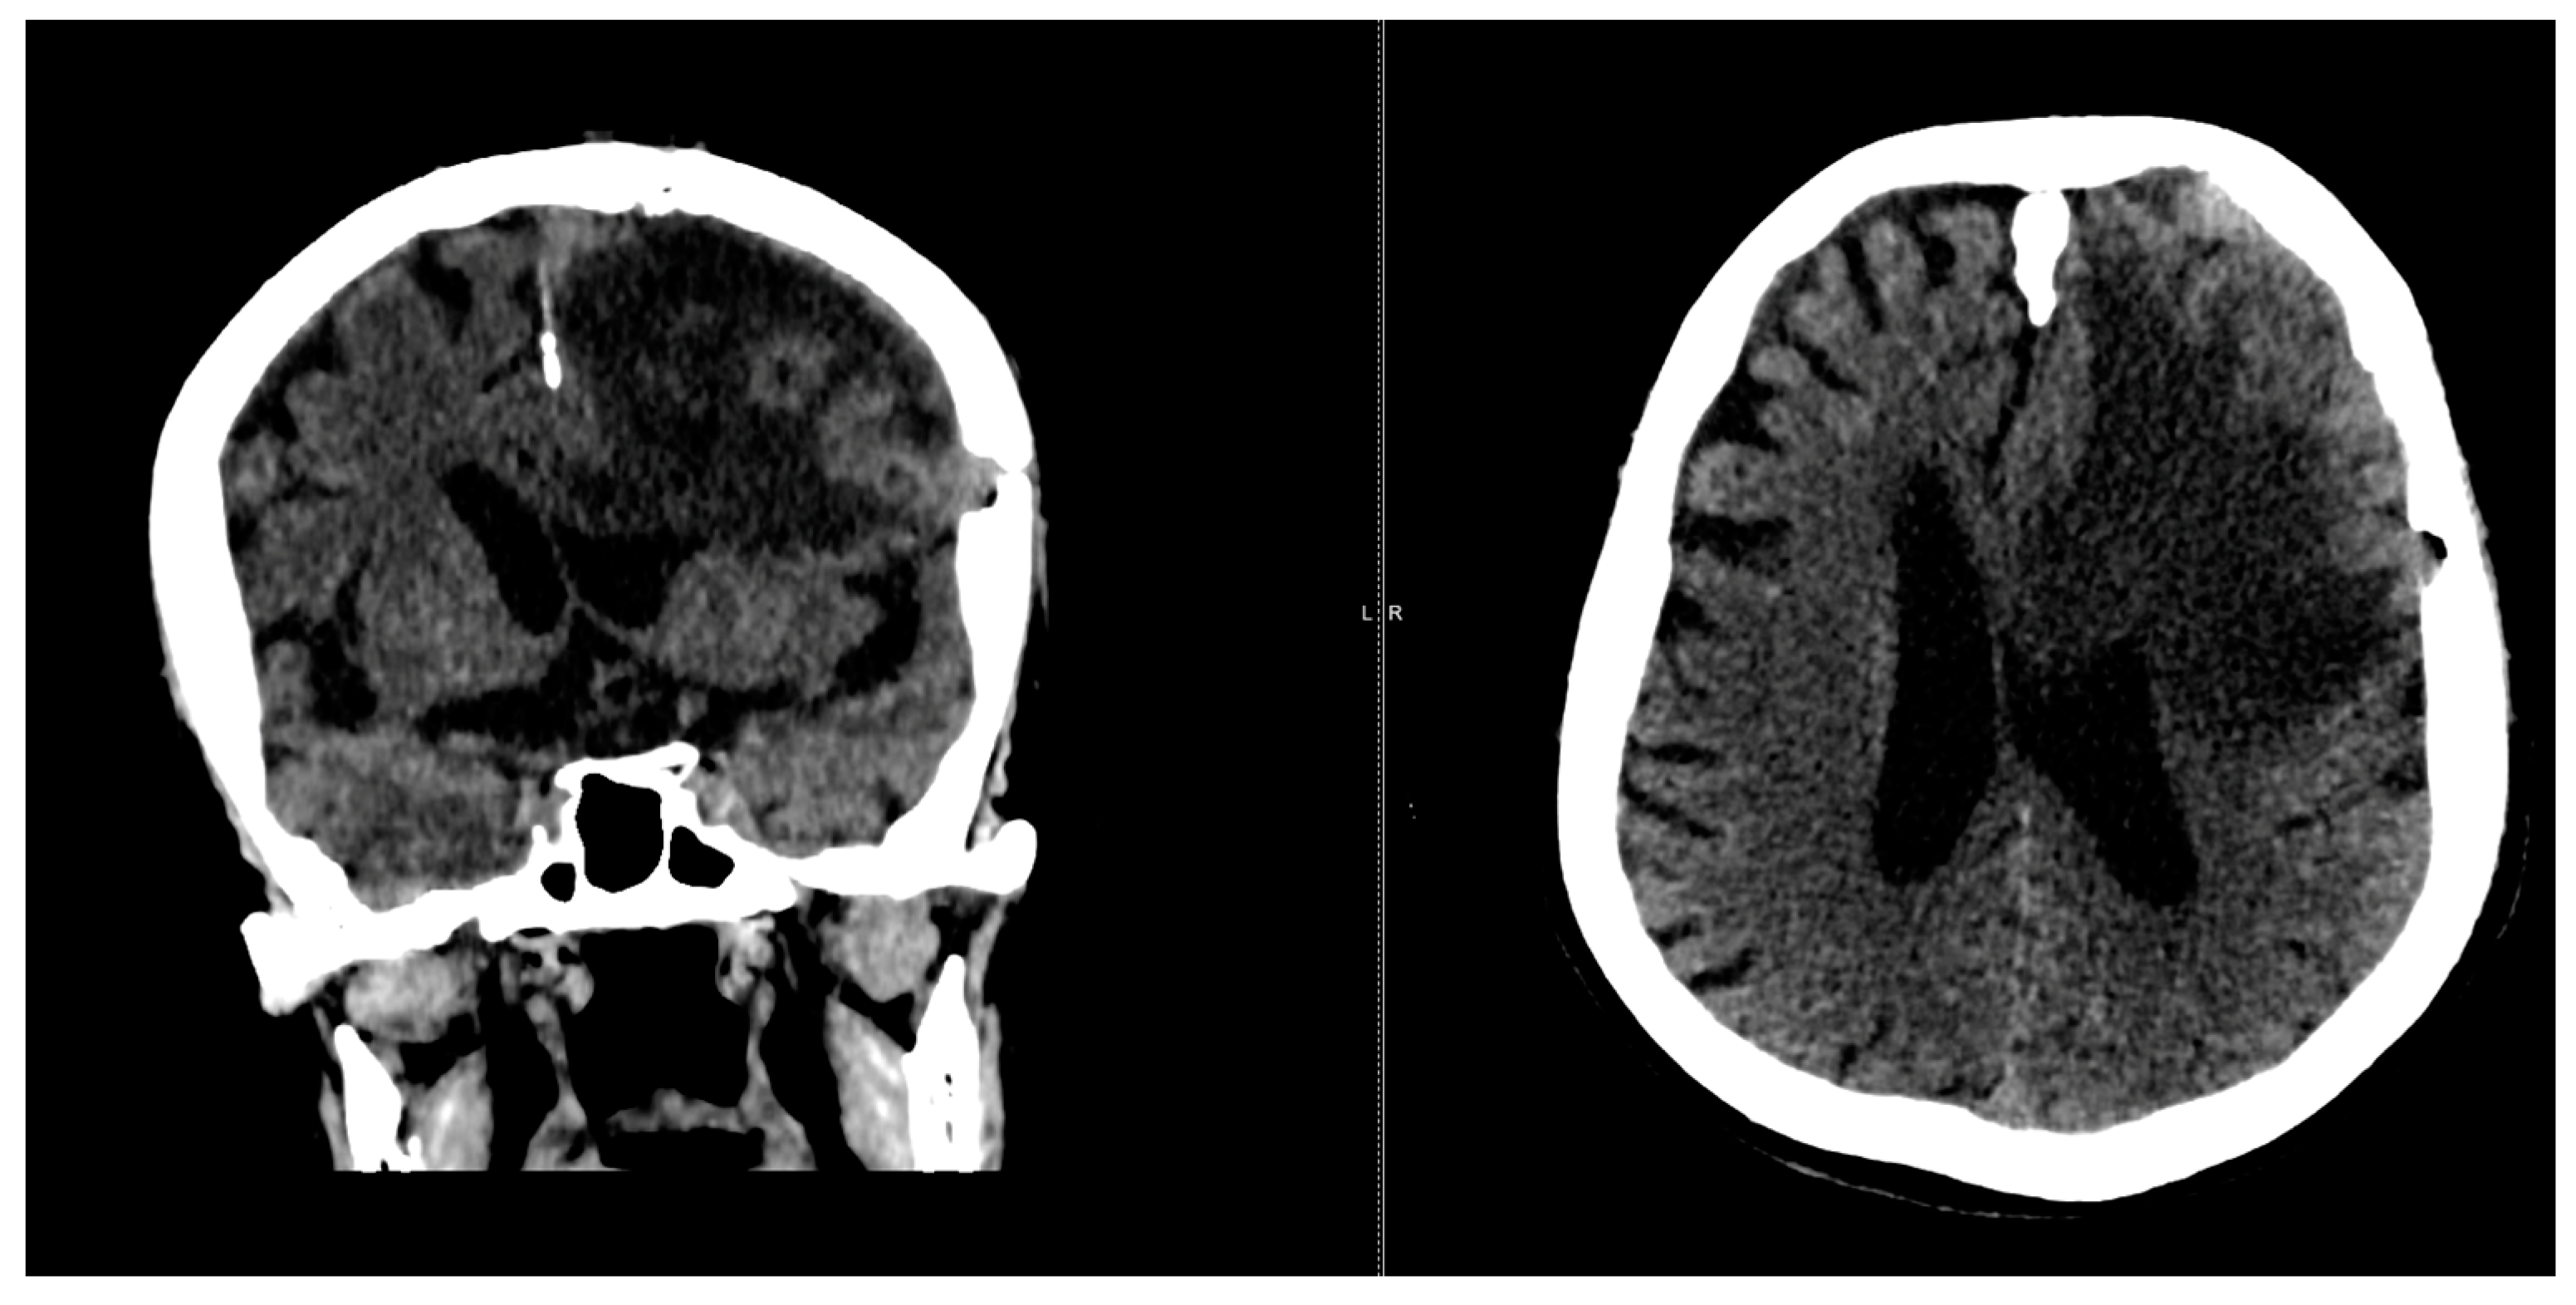

2. Case Presentation